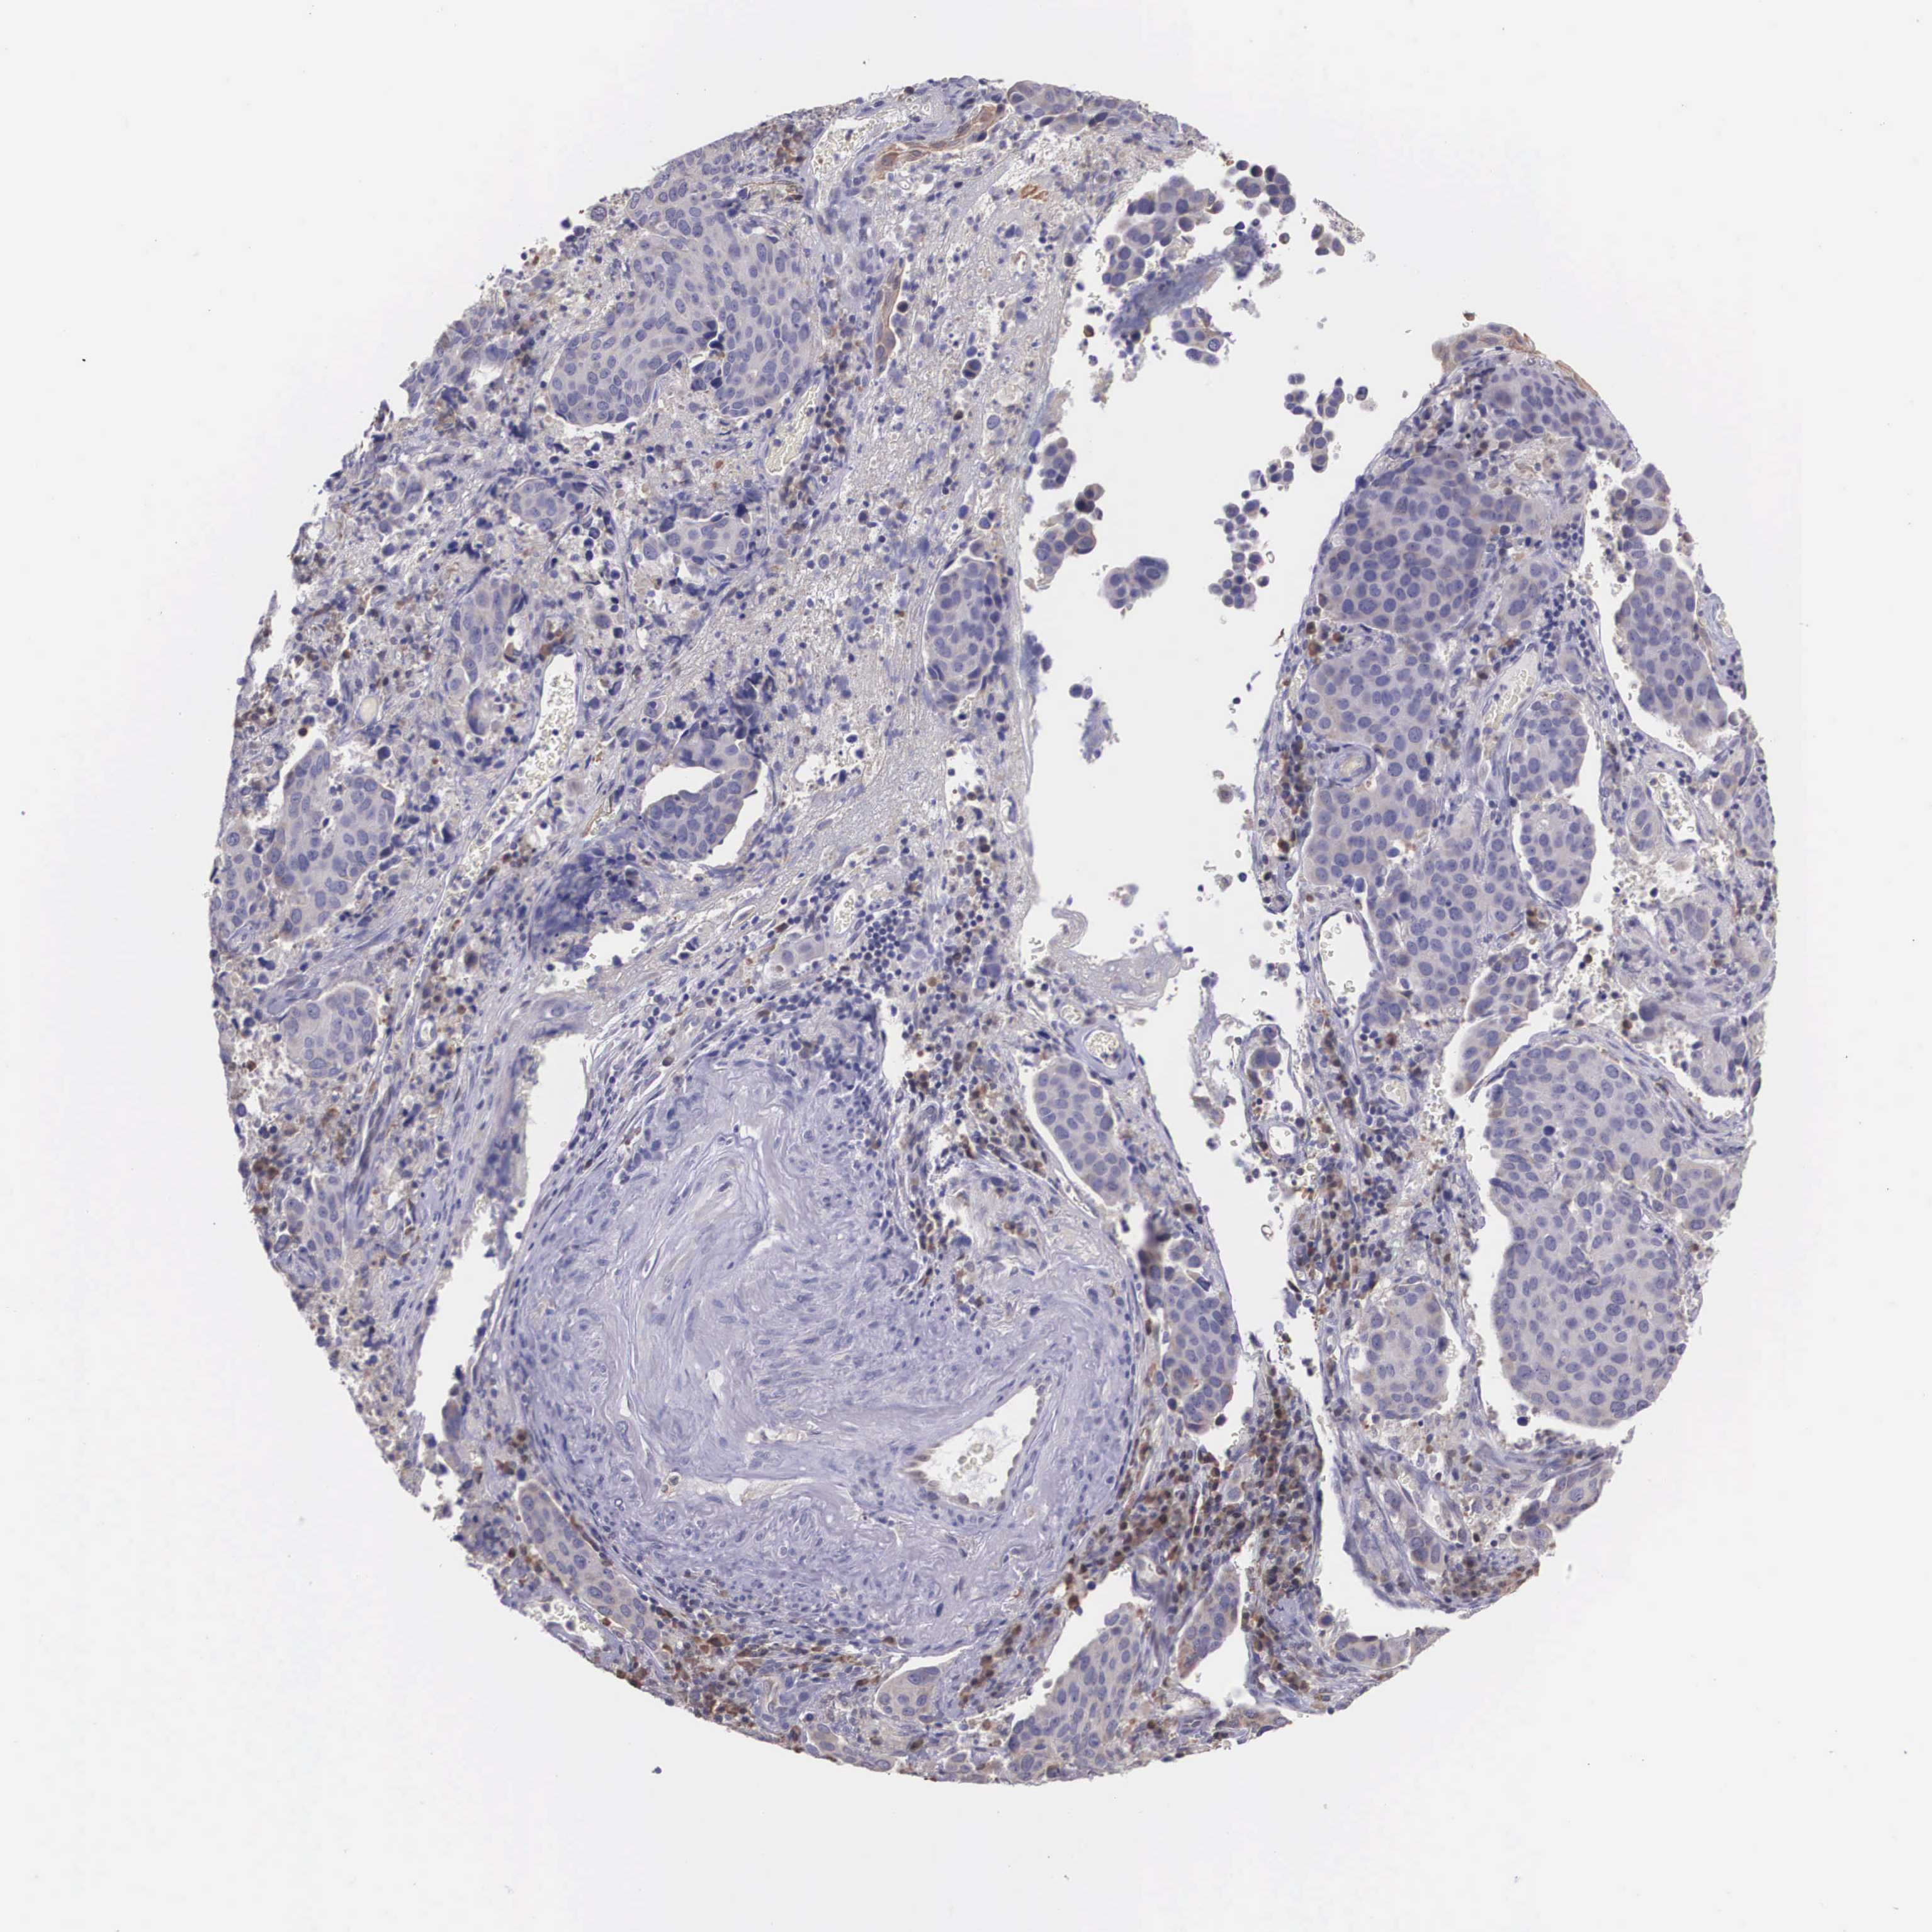

CERVICAL CANCER - Protein expressioni

A mouse-over function shows sample information and annotation data. Click on an image to view it in a full screen mode. Samples can be filtered based on level of antibody staining by selecting one or several of the following categories: high, medium, low and not detected. The assay and annotation is described here.

Note that samples used for immunohistochemistry by the Human Protein Atlas do not correspond to samples in the TCGA dataset.

Antibody stainingi

Antibody staining in the annotated cell types in the current human tissue is reported as not detected, low, medium, or high, based on conventional immunohistochemistry profiling in selected tissues. This score is based on the combination of the staining intensity and fraction of stained cells.

Each image is clickable and will lead to virtual microscopy that enables deeper exploration of all samples and also displays staining intensity scores, fraction scores and subcellular localization as well as patient and tissue information for each sample.

Antibody HPA000662

Staining

High

Medium

Low

Not detected

Intensity

Strong

Moderate

Weak

Negative

Quantity

>75%

75%-25%

<25%

None

Location

Nuclear

Cytoplasmic/membranous

Cytoplasmic/membranous,nuclear

Adenocarcinoma, NOS